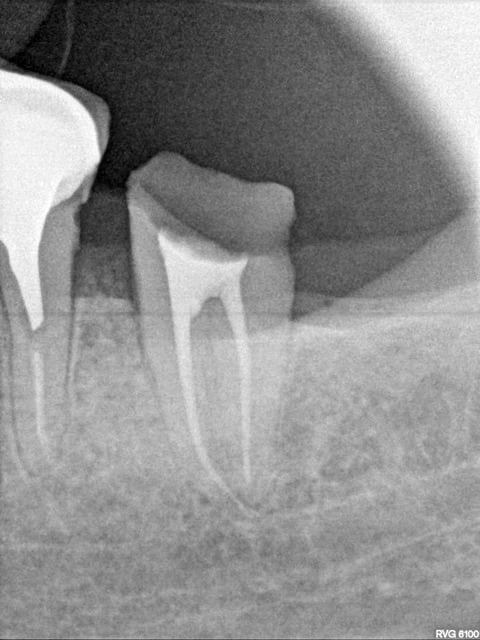

Pour moi l'image de marque du cabinet ne se voit pas. Par contre ca me gênerait de faire une provisoire sur une endo pourrie comme j'en vois souvent -)))

Capture d e cran 2016 01 21 16.30 - Eugenol

Tiens mon cher Bjorn , amuse toi , elle date de ce matin tout frais moulu . Mince, prends une loupe, ça dépasse ? manque un canal ? pas la digue ? rhaaaa je vais en enfer ou j'ai encore le droit de poster ?

Chicot faut m'excuser j'ai pas les photos !

Il y en a qui en mettent trop de la gutta et d'autres pas. Ca fait une moyenne. -))

tiens ? mais je vois qu'on fait aussi des inlay core ! -)

Capture d e cran 2016 01 21 17.43 - Eugenol